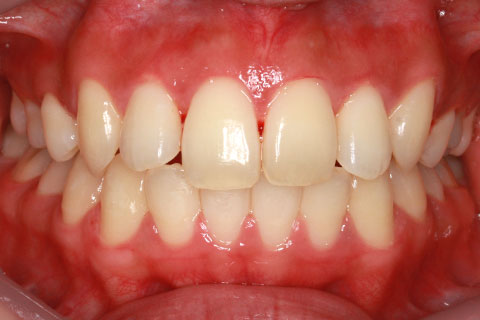

ハーフリンガル矯正3:上の歯のみ舌側矯正で治療(矯正期間24ヶ月)

治療後

- 年齢・性別

- 25歳女性

- 治療期間

- 2年0ヶ月

- 抜歯

- 上下4番抜歯

- 治療費

- 110万円

- 治療内容

- 施術の副作用(リスク)

- 表側矯正と比較して、力学的な操作性が複雑なため、ボーイングエフェクトを起こしやすい。